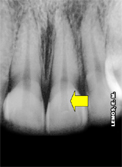

Para a seleção da broca utilizada para a CA devemos levar em consideração o volume da cãmara pulpar, valendo-se da radiografia de diagnóstico, seta amarela: |

| Broqueiro endodôntico para CA e Preparo Cervical | Brocas AR esféricas diamantadas: 1011, 1013 e 1015 - seleção do tamanho | Volume da câmara pulpar |